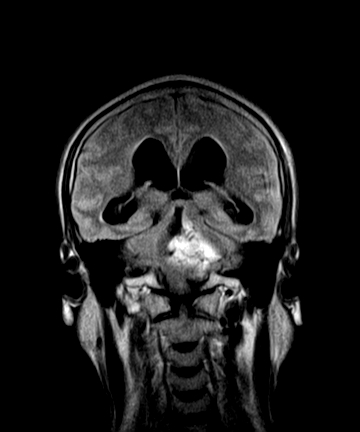

标题: MRI2064:少见病例。男性52,视力下降多年。 [打印本页]

标题: MRI2064:少见病例。男性52,视力下降多年。

四脑室区见混杂信号占位影,脑室系统扩张明显,临近结构显著受压称位,患者52岁,多考虑室管膜瘤可能性大

考虑第四脑室室管膜瘤并梗阻性脑积水;部分性空蝶鞍;左侧上颌窦粘膜下囊肿。

考虑第四脑室室管膜瘤【血供丰富血管母细胞瘤可能】并梗阻性脑积水;部分性空蝶鞍;左侧上颌窦粘膜下囊肿。

小脑蚓部胶质脑膜瘤突入四脑室;肿瘤内见血管流空信号和钙化信号.

比较典型的脉络丛乳头状瘤并脑积水,鉴别小脑蚓部血管母细胞瘤。